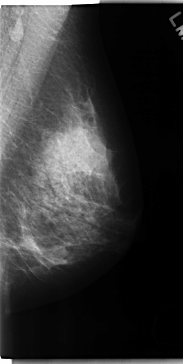

C_0162_1.LEFT_MLO

LEFT_MLO LINES 4728 PIXELS_PER_LINE 2376 BITS_PER_PIXEL 12 RESOLUTION 50 NON_OVERLAY